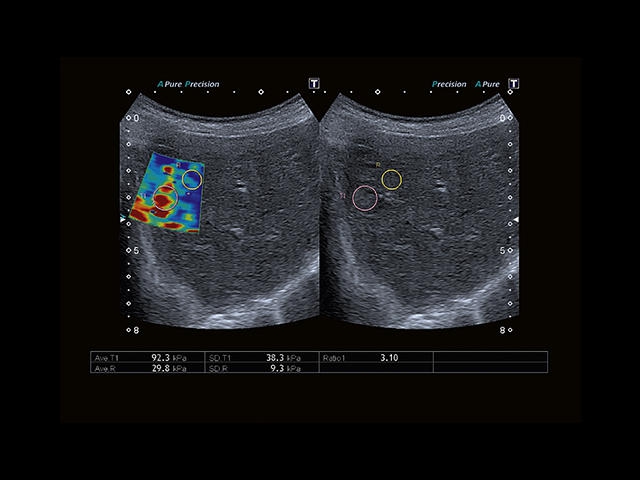

Обновленная версия легендарного УЗ-сканера. Стационарный аппарат экспертного класса Aplio 500 Toshiba NEW, визуализирует анатомические структуры в высоком разрешении. Модель позволяет выявить микрокальцификаты, новообразования, нарушения в работе сердца, сосудов и мышц. Присутствует функция виртуальной эндоскопии, 4D-сканирования, эластометрии тканей, УЗИ с контрастированием. За повышение качества изображения отвечают технологии ApliPure и Superb Microvascular Imaging. Первая задействует возможности пространственного и частотного кодирования, формирует цельный визуальный ряд с сохранением клинических маркеров. Вторая улучшает отображение микрососудистого русла, используя доплеровский эффект. Модель оснащена 21-дюймовым монитором, имеет 4 активных порта. Возможно подключение педиатрических, интраоперационных, лапароскопических и чреспищеводных датчиков.

- SMI. Опция, упрощающая визуализацию микроциркуляторного русла. С ее помощью обследуются сосуды с низкой интенсивностью кровотока, изучаются наиболее тонкие структуры. SMI упрощает диагностику новообразований, минимизирует вероятность ошибки.